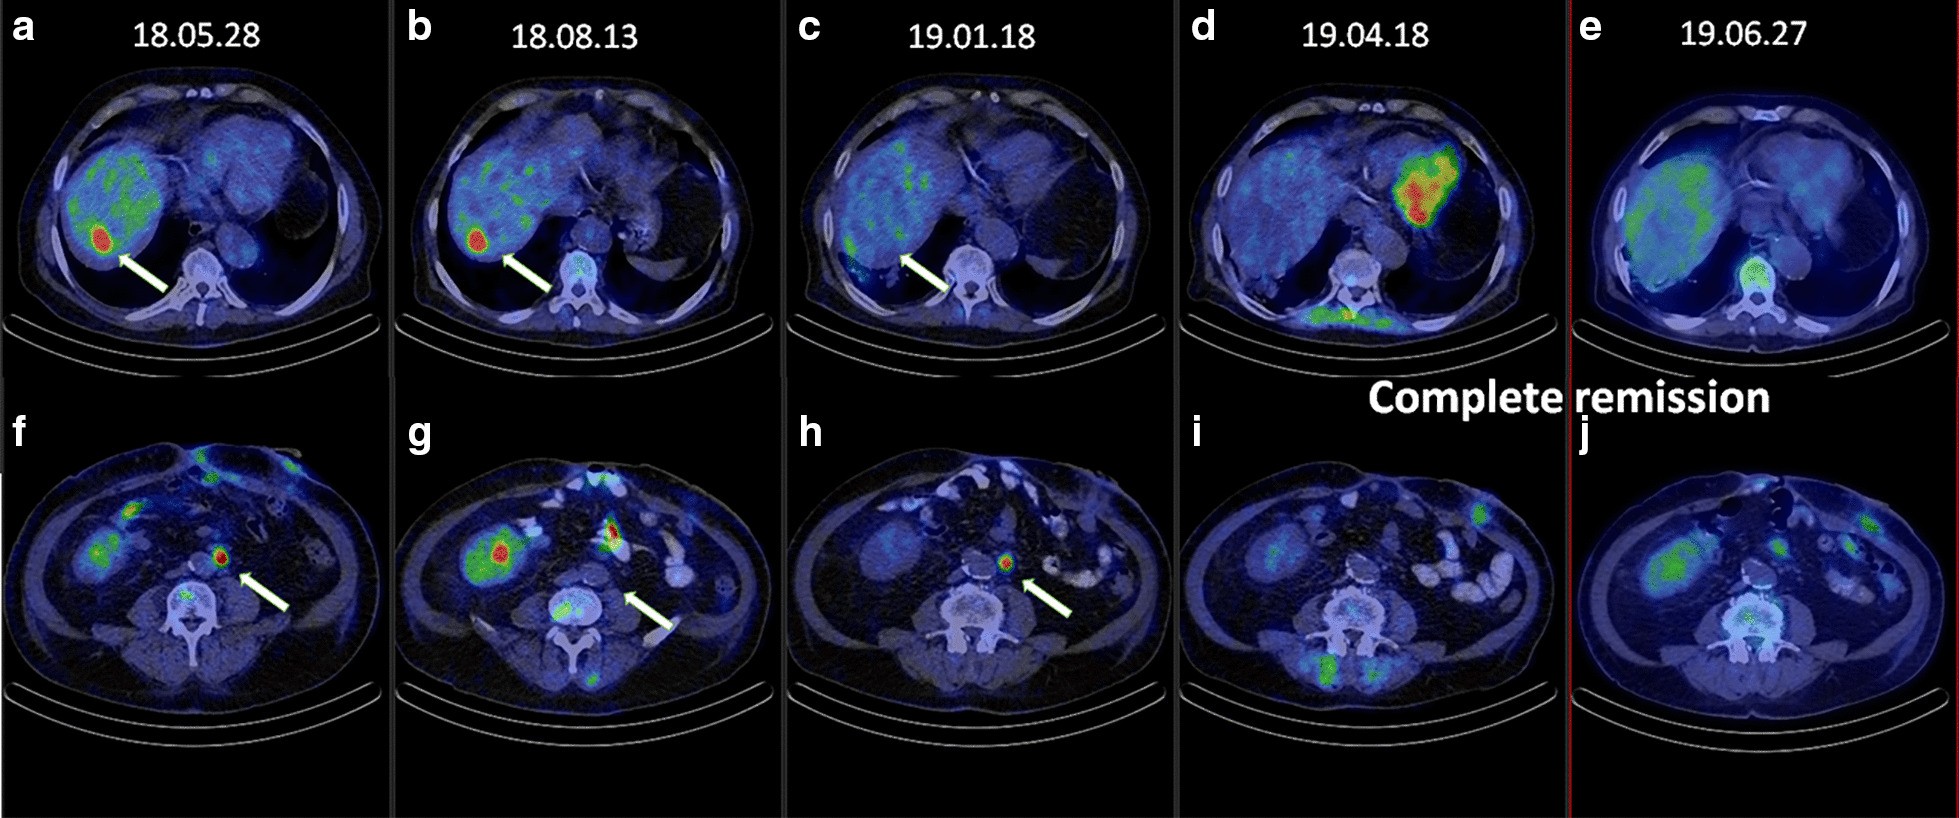

Fig. 2

PET/CET scan images of the targets, the liver and the paraaortic (PAO) region in the different stages of treatment. a, f Image after surgery: visible metastases in the liver and PAO region (May, 2018). b, g Following targeted therapy plus FOLFIRI treatment: stable disease in the liver, the paraaortic lesion shows significant regression (August, 2018). c, h Following stereotactic body irradiation (SBRT), the lesion in the liver shows significant regression (January 2019). d, i Following SBRT of PAO region and concurrent mono-panitumumab treatment: signs of complete remission (April 2019). e, j June 2019: complete remission (June 2019)